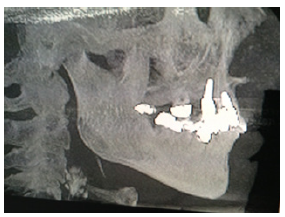

Cone Beam Computerized Tomography (CBCT) is a necessary adjunct for the dental practitioner in being able to see the bone and surrounding anatomy present in a three-dimensional aspect. This allows for better and safer pre-treatment planning of a projected dental implant. No patient, especially geriatric patients, should have an implant placed without first using this modality. The accompanying CBCT [9] (Figure 7) of one of this author’s older patients shows a graded scale in the top center portion of the picture. The author intends to replace a maxillary second molar. The dark area above the first molar is the maxillary sinus with approximately 4mm of bone present on the distal aspect. This is the minimal amount of bone to do a crestal sinus approach. In actuality, on preparation with a crestal approach for a sinus lift, there was approximately 10mm of bone present and an 11.5mm implant was placed into the sinus and with bone and without perforation.

Figure 7: CBCT of the right maxilla area prior to implant placement for tooth #2. From: Patient records of Eric Shapira DDS with permission from C. Voss. ©.

Figure 8: Radiograph showing implant placement into maxillary sinus with bone graft. From: Patient records of Eric Shapira DDS used with permission©.

A photo of a similar crestal approach sinus lift in the maxillary right quadrant is seen with an implant placement (Figure 8) [10]. On the CBCT scan, a corresponding number will allow the practitioner to look at a tomographic side view of the area to be grafted. The cross-sectional pictures allow one to see the width and direction of the bone. Today with “Guided” Implant Surgery, the procedure is effortless compared to the past. A surgical stent is made utilizing the 3-D CBCT on six axis’s and all the surgery is done through the stent that guides the drill of the practitioner to the proper length and direction the implant should be placed with respect to the local anatomy around it. This procedure is virtually painless and heals in short-order.